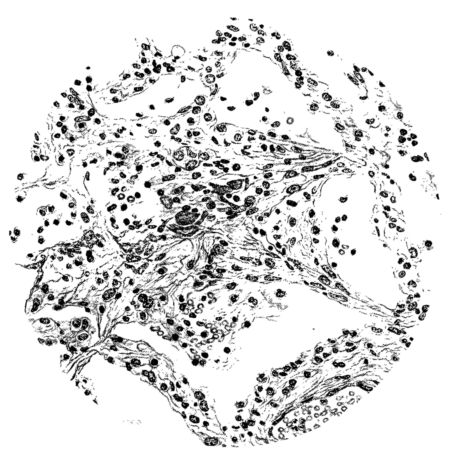

No matter what the portion of the lung from which the sections are derived, the fundamental changes found are the same. The subpleural sheets are spread wide apart, now by empty spaces, now by coagulated fluid. The process extends from the surface through the interlobular septa (Fig. XX), and is accentuated where the connective tissue is more prominent around vessels and bronchi. The nature of the infiltrate in the subpleural and interstitial tissues becomes more evident in the alveoli, which likewise are filled. The material varies somewhat in appearance, probably dependent upon its proteid content. Not infrequently the alveoli contain a homogeneous, pink-staining mass, which resembles the colloid of the thyroid gland. Again, it may be simply a coarse granular precipitate (Fig. XXIII), and in still other instances, small sticks and strands form the bulk of the alveolar content (47, 92, 140, 156). This subpleural, interstitial, perivascular, peribronchial, and alveolar edema, which is a term applicable to this collection of fluid, is very prominent, and although its intensity varies in different portions of the lung; and although it may be replaced in some areas by other types of exudate, unquestionably, this is the dominating expression of the inflammatory process in the early stage of the disease.

As might be expected from the gross appearance, the alveoli vary in size. At times slightly collapsed and at other times overdistended, their lumina are still the seat of the inflammatory exudate, although the mechanical change may allow of some variation in the appearance of their walls. As a rule, however, the alveolar wall is prominent and owes its conspicuousness to the tortuous, engorged vessels within. These vessels contain red blood cells almost exclusively, and on account of the partial, occasionally complete, loss of the lining epithelium, the alveolar wall appears as a huge, dilated arteriole (101) separating the lakes of coagulated material in the spaces (Fig. XXIII). There are areas, as indicated above, where the alveolar content may be more definitely arranged in the form of beaded or homogeneous strands of different caliber; the smallest resemble delicate threads. They tend to converge toward the alveolar wall like wheat in a sheaf, and often pass through this wall by way of the so-called pores of Cohn; as soon as the body of the neighboring alveolus is reached, they again present a fan-like expansion into innumerable, fine strands (Fig. XXII). Where the exudate is more fibrinous, the alveolar wall is less likely to be distended, its vessels are not so prominent, and their content of red blood cells is definitely decreased. Still this is not the most extreme type of alveolar exudate met with at this stage. Perhaps, the most striking, although not the most frequent, exudate has a superficial resemblance to a huge, red blood clot, and it may be difficult to make out the alveolar walls separating the masses of well preserved red blood cells that fill the alveolar spaces. These areas are indistinguishable from infarcts and may be associated with thrombotic arteritis in near-by pulmonary vessels (47) (Figs. XXIV and XXV). Among the red blood cells an occasional strand of fibrin, a desquamated alveolar epithelial cell, and rarely a polymorphonuclear leucocyte may be encountered. The alveolar wall itself varies in the definition of its outline. When its vessels are greatly distended, when its alveolar epithelium is gone, and when its content consists largely of red blood cells, it is difficult to distinguish from the exudate which it encloses. However, when it is more compressed or when its epithelial lining cells are still more or less intact, it may be seen as a blue-staining strand under the low power of the microscope, for the well preserved nuclei lend it prominence.

21There are, of course, variations in the extent of the serum, the fibrin, and the hemorrhage in the exudate of the alveoli, and while these different types may occur as pure forms, often they are associated. In still other areas and varying in prominence, one finds as characteristic an exudate, not only of serum, strands of fibrin, and red blood cells, but also a diffuse dotting of the exudate with bacteria, singly, in pairs, clumps, and chains (92, 164) (Fig. XXI). This type of reaction is uncommon in pulmonary disease. It resembles more closely a streptococcus cellulitis such as is encountered frequently in the subcutaneous tissues, for example, a woody phlegmon, or a sero-hemorrhagic exudate like the avirile response to a rapidly fatal hemolytic streptococcus serositis. A similar reaction has been reproduced experimentally in animals which have been rendered aplastic with benzol previous to pulmonary insufflation, and it is conceivable that the lack of polymorphonuclear response in the inflammatory exudate may be associated with some such general destruction or temporary suspension of leucocytic formation (160).